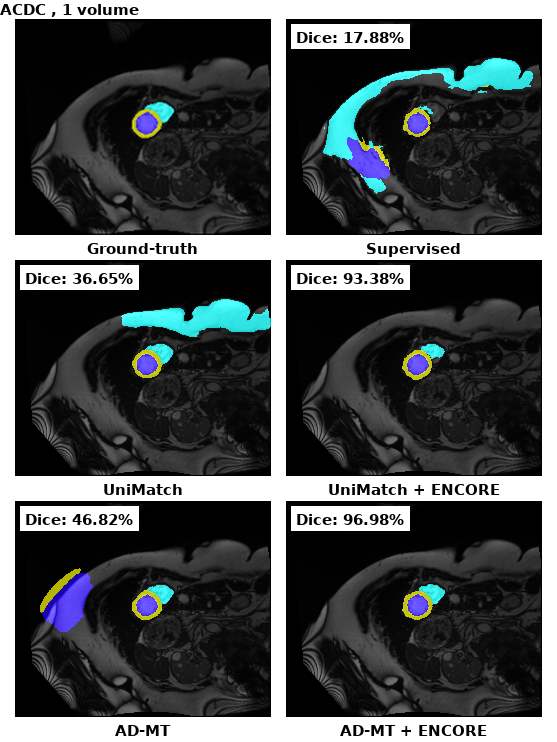

For multi-class segmentation in the ACDC dataset (Table 4), ENCORE further demonstrated its effectiveness in low-data settings. UniMatch + ENCORE trained with only one labeled volume outperformed supervised training with 10 labeled volumes. As expected, performance gains with ENCORE were most pronounced in extreme low-data settings (one and two labeled volumes); however, improvements remained consistently high across different semi-supervised learning frameworks.

Figure 4 presents qualitative comparisons between different baselines with and without ENCORE. Notably, for the LA dataset, integrating ENCORE into both UniMatch and AD-MT enhances the retrieval of important structural features in volumetric segmentation.